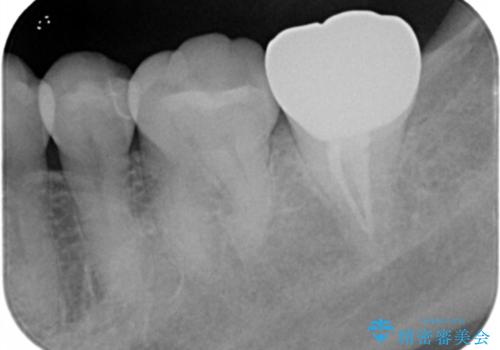

過去にプラスチック樹脂の治療がされており、プラスチックと歯質の隙間に汚れがたまり黒くなっていました。

プラスチック樹脂は安価で治療時間も一回で終わるが歯質との隙間ができやすく虫歯の再発のリスクが高いです。また、吸水性なので何年か過ぎると劣化します。

セラミックは歯質との隙間ができにくく虫歯の再発のリスクをさげ劣化防止にもなります。